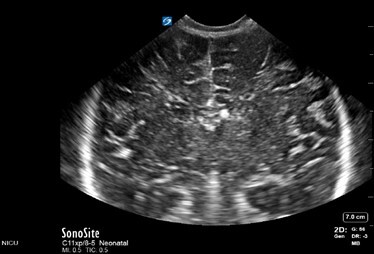

Neonatology Normal Anatomy Depth Too Low Image